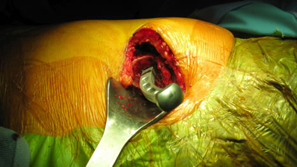

He was in his usual state of good health until age 14 when he became spontaneously septic. He was placed on ID pressors and subsequently lost his toes from vasoconstriction. He developed AVN of the femoral head. He does not think he was on any prednisone. He was then treated with a hip fusion. During the hip fusion the surgeon decided to do a subtrochanteric osteotomy which left the patient with a deformed proximal femur. He was placed in a hip spica cast for over 5 months. He believes he was also infected in the cast, but after speaking to him it sounds as if he had wound breakdown from the cast and not a deep infection.

Modified Anterior-lateral Watson-Jones surgical approach. |

| Removal of Hardware (two screws) |

Level and orientation of osteotomy is critical to the entire surgical case |

Cup orientation and preparation is challenging and care should be taken not to penetrate the medial wall. Proper cup placement is difficult do to loss of bony landmarks. Hip abductors will be weak and joint instability is a significant concern. Lateralization of the femoral component will aid in reducing forces across the hip joint potentially reducing limp and post-operative hip dislocation.